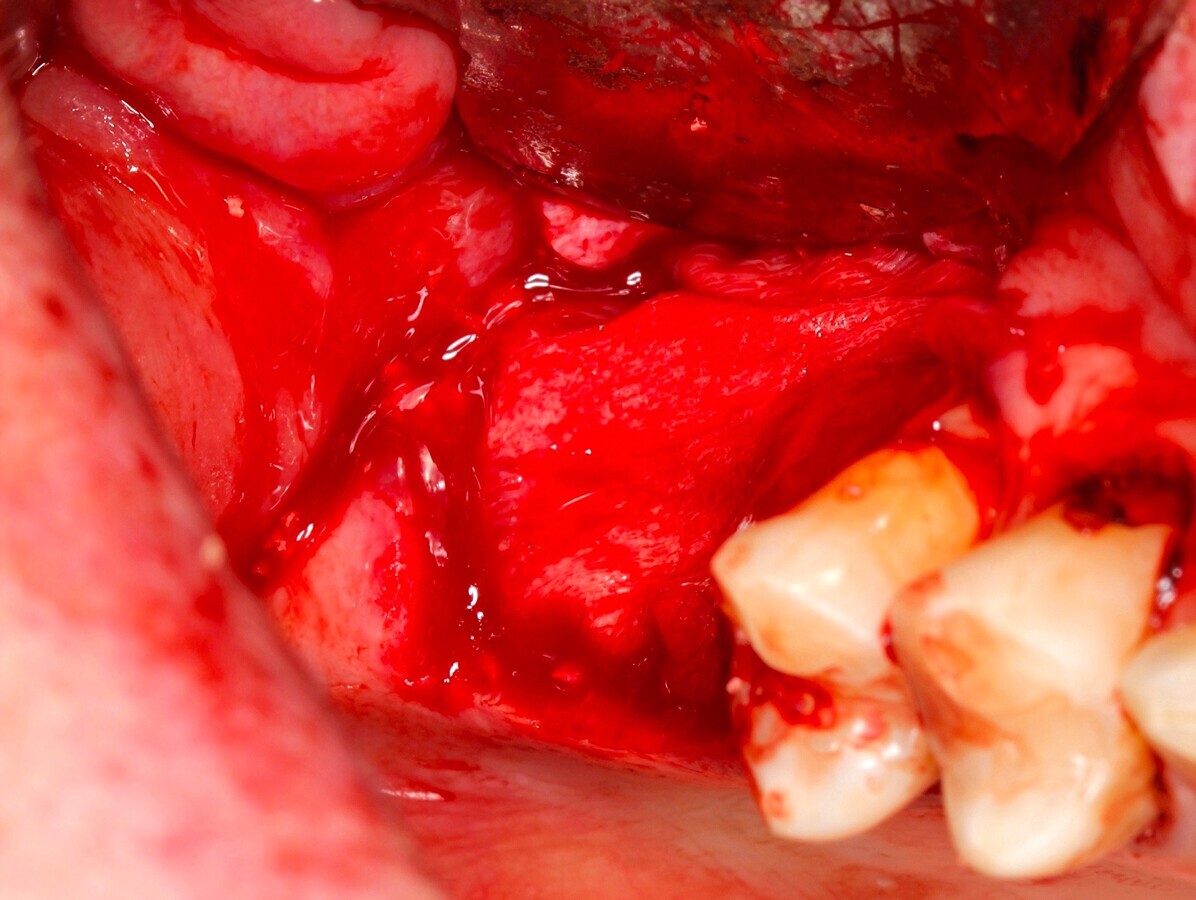

Fig. 20 Figura 20

3. Elevación del  colgajo mucoperióstico a espesor total con periostotomo exponiendo el la tabla vestibular maxilar ligeramente superior a la altura prevista del techo de la ventana lateral.